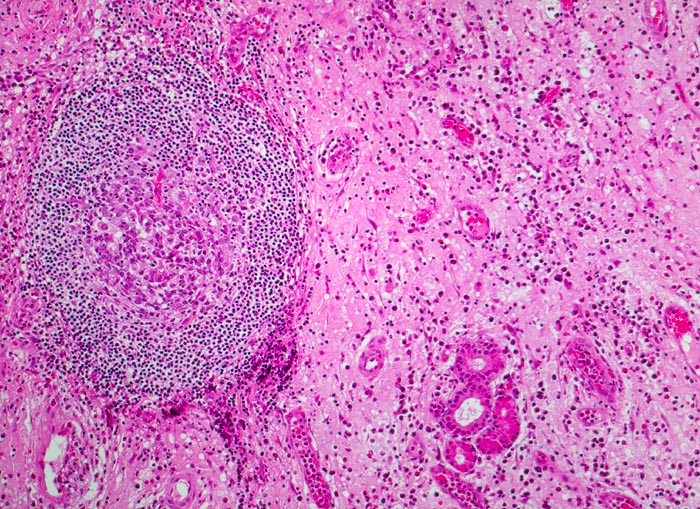

Morphologische Merkmale:

• Polypoides Gewebsfragment bedeckt von mehrreihigem Flimmerepithel.

• Herdförmige Schleimhauterosionen.

• Ödematöses Stroma mit gemischtem Entzündungsinfiltrat: Lymphozyten, Plasmazellen, Histiozyten und zahlreiche eosinophile Granulozyten.

• Im Zentrum des Polypen Drüsenläppchen und zahlreiche Blutgefässe.